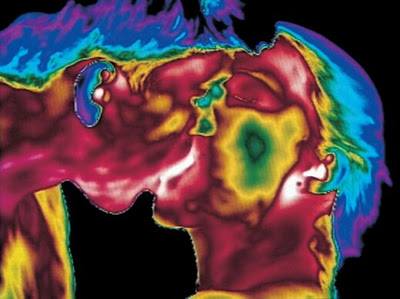

Մարմնի ջերմաստիճանը